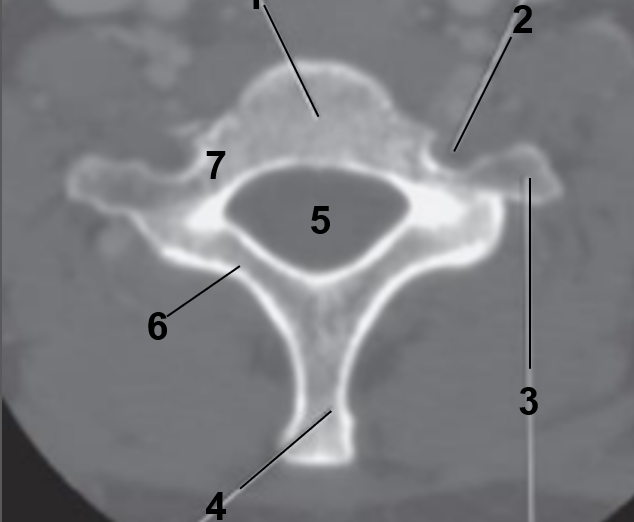

1

Transverse foramen

2

Anterior arch

3

Transverse Process

4

Posterior arch

5

Superior articular facet

6

Dens

7

Vertebral Foramen